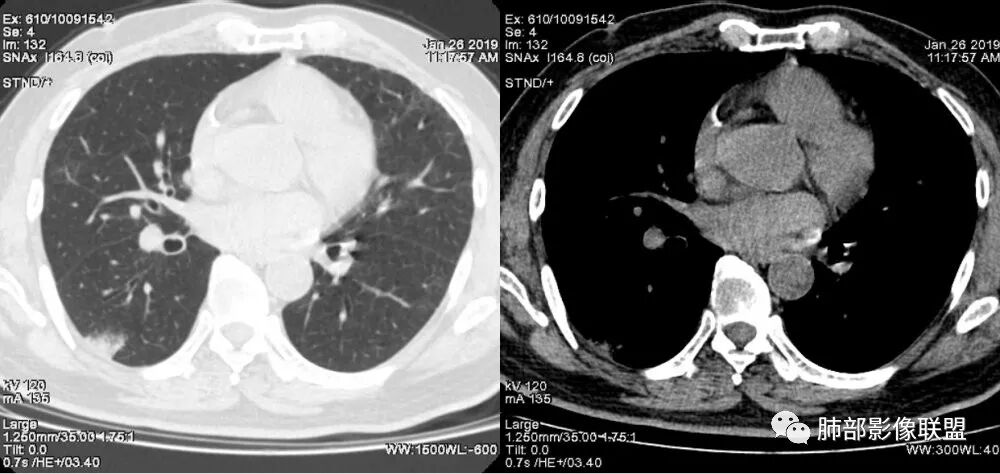

中年女性,右肺下叶沿胸膜下大片状高密度影,实变加GGO,外朝内发展,边界较清,内可见蜂窝征及枯树征,考虑肺炎型肺癌。

右肺病灶,病灶较大,实性+周边ggo,边界清晰,胸膜下分布,长轴平行于胸膜,内部支气管充气征,因不发热,暂不考虑感染性病变,支持肺炎型肺癌。

女性,咳嗽咳痰不发烧,右下外基底段实变影,边缘清楚GGO,有充气支气管征,枯树枝不明显,由外向内;诊断:肺炎型肺腺癌;鉴别:1、肺栓塞(外型神似,但无胸痛丶咯血);2丶肺炎

老年女性,右下肺实变影,糊墙,外朝内发展,病灶里有小叶内间质增厚,周围边界清楚了GGO,支气管扩张明显,考虑粘液癌;不符合点,支气管扩张太厉害了,鉴别淋巴瘤。

患者中年女性,咳嗽咳痰就诊。胸部CT:右肺下叶后基底段片状实变影,由胸膜向内发展呈扇形,病灶里有小叶内间质增厚、蜂窝状影,周围边界清楚GGO,内可见扩张支气管,淋巴结无明显肿大。综合符合粘液腺癌。

我觉得纵膈窗可以更好观察,纵窗看支气管很紊乱的感觉,鉴别,肺炎的支气管充气征,支气管走形还是很自然的

老年女性,咳嗽、咳痰。右肺下叶沿胸膜下大片状高密度影,外周磨玻璃影,边界较清,小空泡,蜂窝征及支气管充气征,叶间裂串珠征,考虑:肺炎型肺癌,鉴别:肺克,链球菌,NTM等感染。

2.病灶示中央实变区,周围GGO,可见明显小叶间隔增厚,GGO边界清楚,应当考虑到恶性病变的可能性。肺炎因炎性水肿及渗出,影像上边界常模糊不清,注意早期粘液腺癌可出现似清非清的边界。粘液腺癌因粘液成份较多,密度一般偏低,纵隔窗病灶常会消隐或范围会明显缩小,这不同于炎性实变。

3.病灶内支气管走形略显僵直,侧支少(粘液阻塞),也符合肺腺癌的枯树枝征。而大叶性肺炎的支气管是管壁光整、通畅、自然,结核的支气管常常壁增厚,甚至狭窄后扩张;